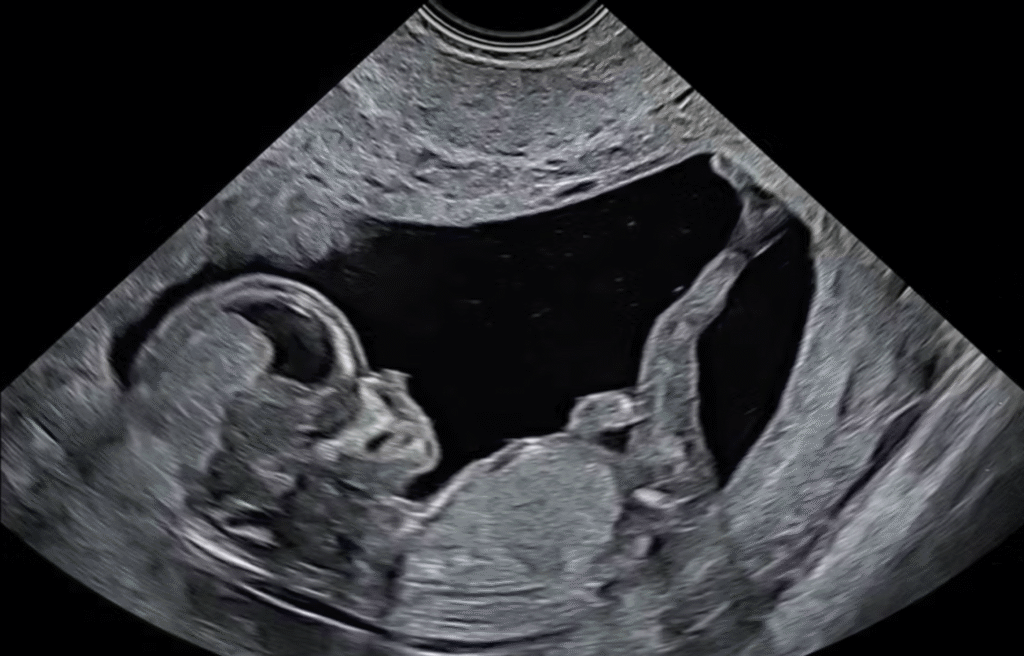

Investigation 4: Preparing for Birth - Late Fetal Development

In this Investigation, students explore the prenatal environment during late fetal development and examine how factors such as amniotic fluid, space constraints, and ongoing maternal support prepare the developing human for birth.